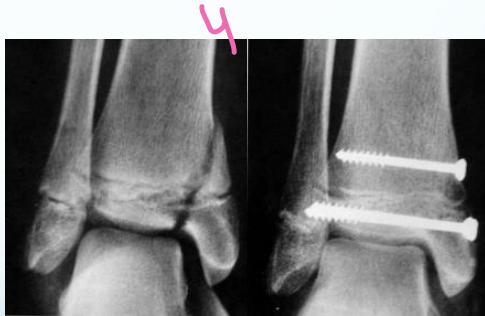

- Type III - Through the physis and extend to intra-articular

- Type IV - Metaphysis + physis + Intra-articular

Intra-articular (Type III / IV)

- Anatomical reduction and internal fixation